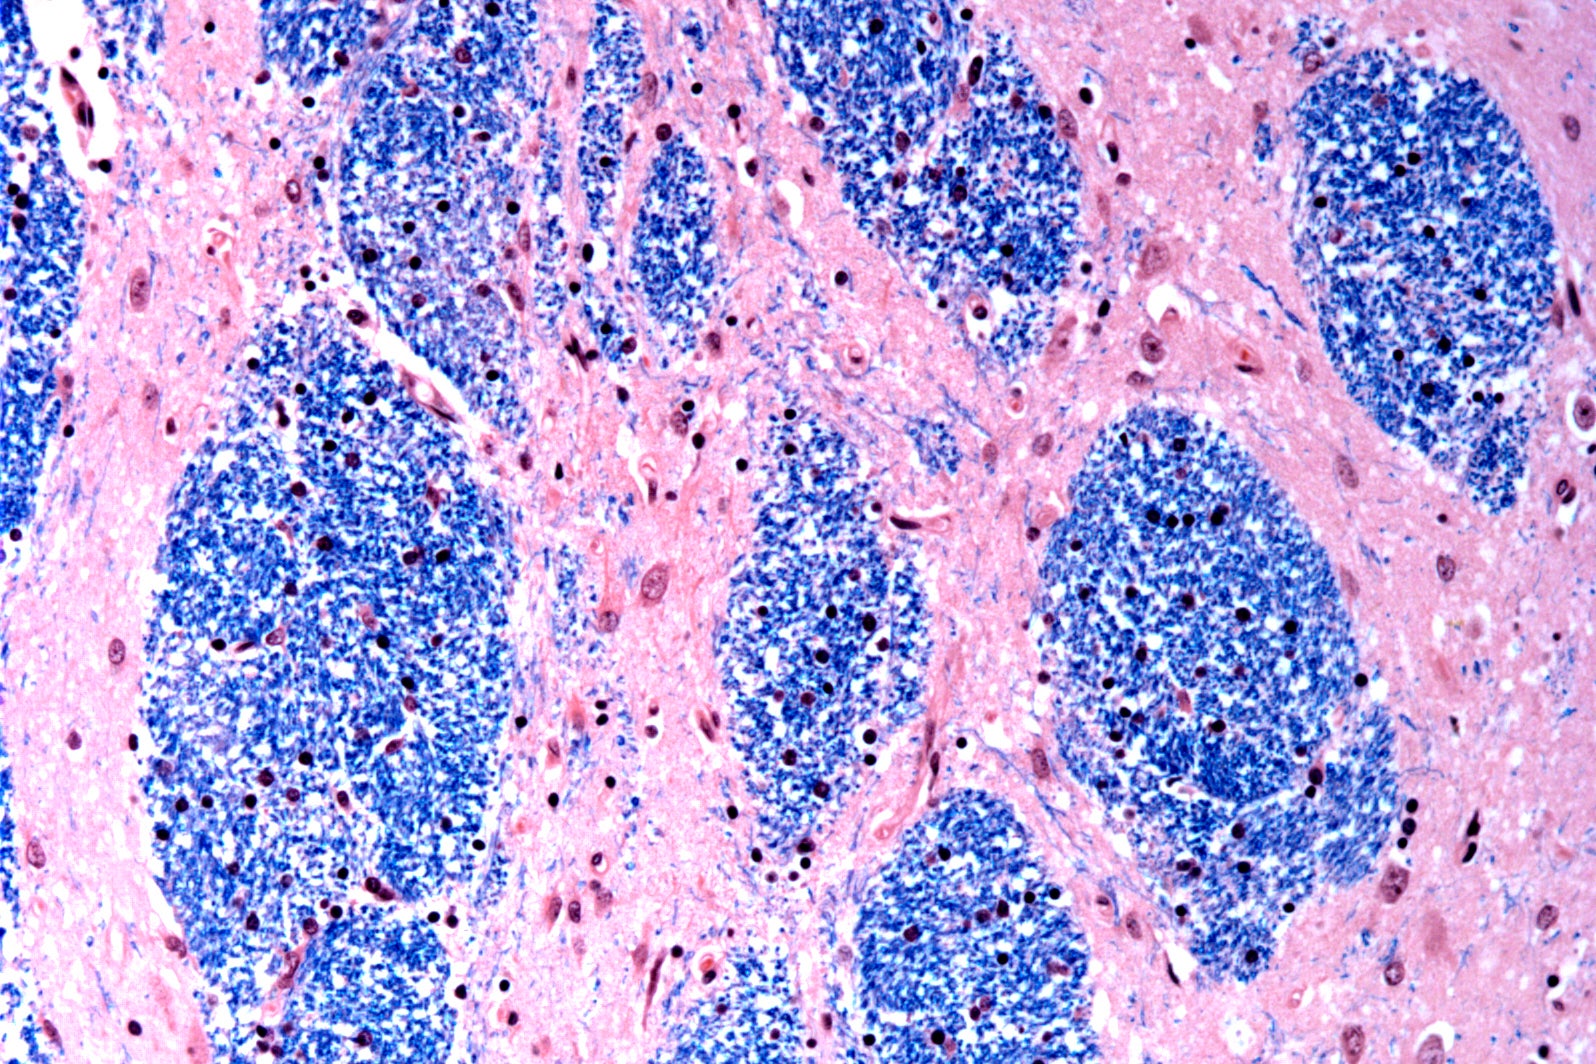

Scientists at the Broad Institute of MIT and Harvard, McLean Hospital in Massachusetts and Harvard Medical School studied brain tissue donated by 53 people with Huntington’s and 50 without it, analyzing half a million cells.

They focused on the Huntington’s mutation, which involves a stretch of DNA in a particular gene where a three-letter sequence – CAG – is repeated at least 40 times. In people without the disease this sequence is repeated just 15 to 35 times. They discovered that DNA tracts with 40 or more such “repeats” expand over time until they are hundreds of CAGs long. Once CAGs reach a threshold of about 150, certain types of neurons sicken and die.